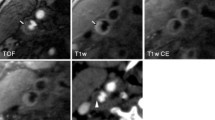

Each ICA was divided into 7 segments (C1-C7) using the Bouthillier classification [30]. Data corresponding to each segment was measured in the 0.63-mm-thick cross-sections reformatted from 3D CMR VWI. A case example is provided in Fig. 1. The following variables were measured from the 3D CMR VWI and corresponding DSA images: 1) lumen diameter (i.e. the lumen diameter of the normal CCA and each ICA segment, stenosis diameter, and reference diameter); 2) stenosis degree (%), calculated according to the North American Symptomatic Carotid Endarterectomy Trial criteria [31]; 3) lesion length, measured as the maximum range of the lesion at the sagittal plane); and 4) presence of ulceration, defined as carotid plaque surface with fissuring or fibrous cap rupture. If a carotid artery had multiple stenoses, the narrowest one was evaluated. The severity of stenosis was subsequently classified according to the following criteria: no stenosis = 0%, mild stenosis = 0–29%, moderate stenosis = 30–69%, severe stenosis = 70–99%, and total occlusion = 100%. Two experienced radiologists (Z.W. and L.W.) blinded to the clinical information and DSA results, performed the above quantitatively analyses on the 3D CMR VWI images.

3D CMR VWI and DSA images of CCA. Both a, a sagittal 3D cardiovascular magnetic resonance (CMR) vessel wall imaging (VWI) image, and b, a lateral projection of a digital subtraction angiography (DSA) image, depict the lumen diameters of the common carotid artery (CCA) and C1-C7 segments in a 59-year-old man. The cross-sectional views at 8 locations are shown with numbered sub-windows, including CCA and internal carotid artery (ICA) (C1-C7). CCA, common carotid artery; 3D CMR VWI, three-dimensional cardiovascular magnetic resonance vessel wall imaging; DSA, digital subtraction angiography; ICA, internal carotid artery

3D CMR VWI and DSA images of CCA of total occlusion. Both a, a sagittal 3D CMR VWI image, and b, a lateral projection of a DSA image depict total occlusion of the internal carotid artery (arrow) in a 67- year-old man. 3D CMR VWI, three-dimensional cardiovascular magnetic resonance vessel wall imaging; DSA, digital subtraction angiography